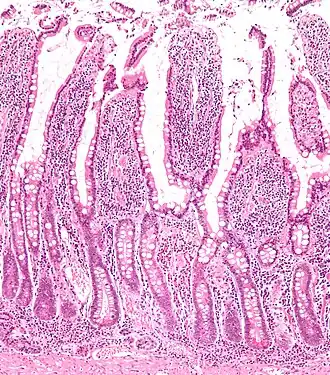

![]() Section of duodenum of a cat. X 60. | |

Intestinal villi (sg.: villus) are small, finger-like projections that extend into the lumen of the small intestine. Each villus is approximately 0.5–1.6 mm in length (in humans), and has many microvilli projecting from the enterocytes of its epithelium which collectively form the striated or brush border. Each of these microvilli are about 1 μm in length, around 1000 times shorter than a single villus. The intestinal villi are much smaller than any of the circular folds in the intestine.